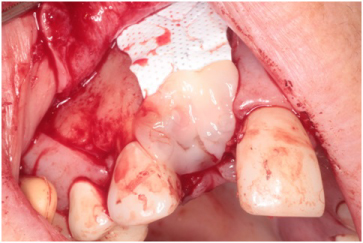

Using bilateral papillae sparing releasing incisions at surgical sites, the Cytoplast® membranes and tacks were removed and the implant sites were prepared showing excellent bone regeneration (Figures 20, Figure 21, and Figure 22). Standard protocol was used to prepare Straumann® Bone Level Tapered implants (Andover, MA, USA). (Figures 20 and Figure 22). Four months post implant placements with all 3 implants osseointegrated and provisional restorations in place. (Figures 23, Figure 24, and Figure 25).

Figure 21: 4-months post-op guided bone regeneration at the #s 9 and 10 sites. Notice the bone regeneration compared to the pre-op condition. View Figure 21

Figure 22: Straumann Bone Level Tapered implants placed at the #s 9 and 10 sites. View Figure 22